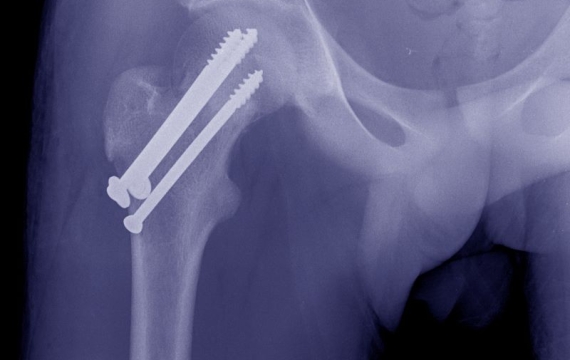

El procedimiento para la cirugía de cadera y pelvis se realiza limpiando el acetábulo de la cadera para retirar el cartílago remanente y el hueso artrítico o que está dañado, se coloca el nuevo acetábulo de la cadera en el lugar que corresponda. El cirujano realizará una reducción de la lesión para volver a juntar los huesos pélvicos, los mantendrá en su lugar colocándole un dispositivo interno, como:

• Tornillos quirúrgicos (Pasadores)

Image

radiografía-de-cadera-en-valencia